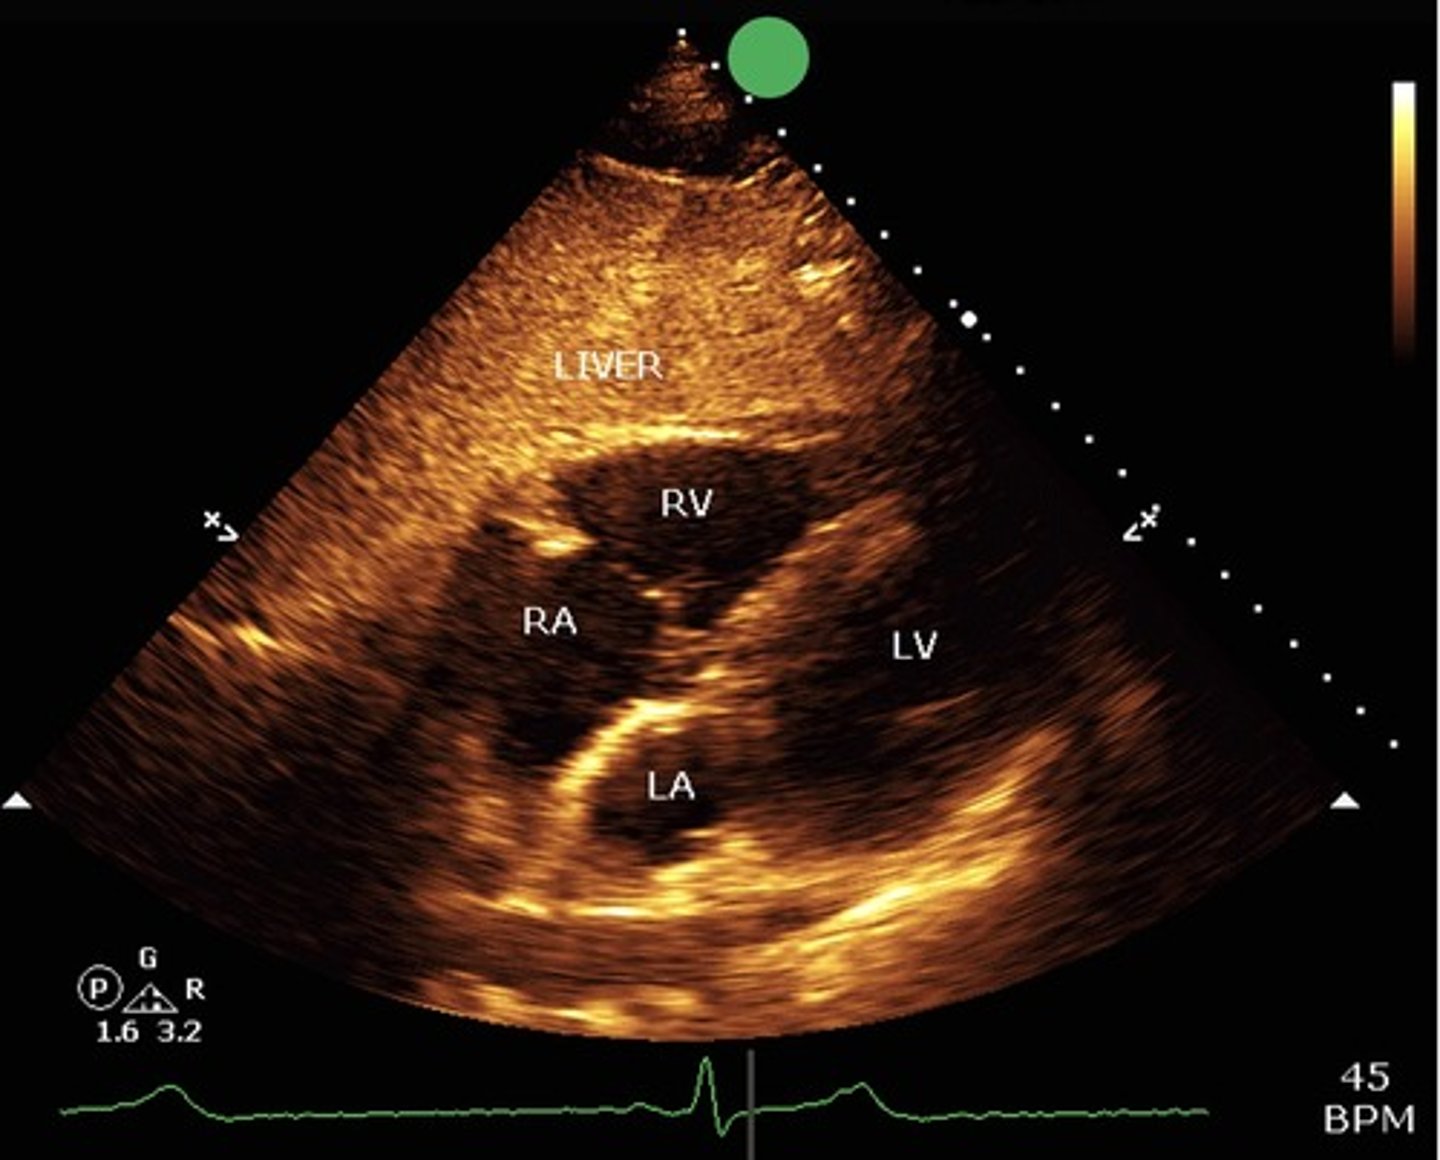

Subxiphoid view

what view is this?

LV, RV, LA, RA, mitral valve, tricuspid valve

what structures are seen with apical 4 chamber view?